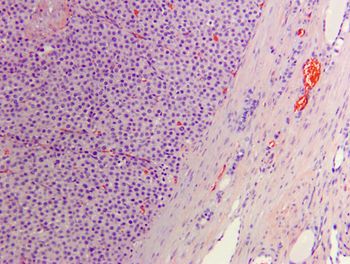

Dr. Caitlin Brown provides the anatomic pathology perspective on this challenging oncology case.

Dr. Lisa Viesselmann provides the clinical pathology perspective on this challenging oncology case.

Dr. Isabella Pfeiffer provides the radiation oncology perspective on this challenging oncology case.